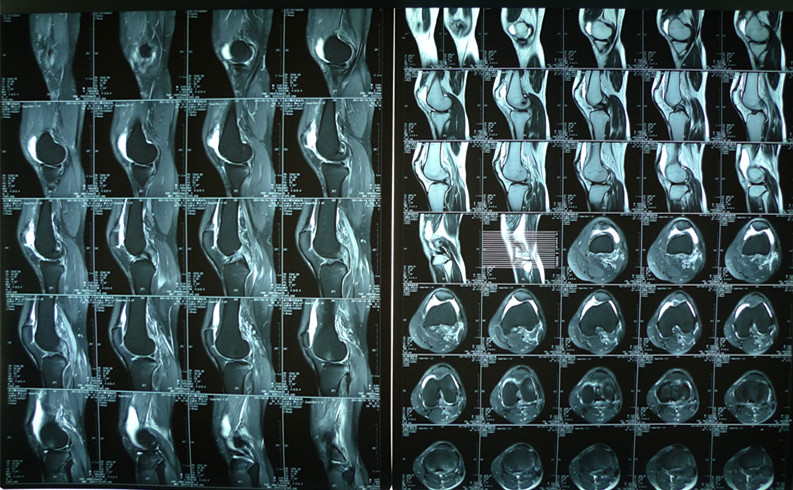

图为患者术前核磁